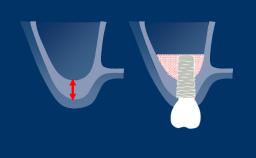

Os aspectos estéticos das próteses sobre implantes ganharam crescente atenção e importância nos últimos anos. Há vários fatores que determinam se as próteses sobre implante são consideradas esteticamente bem-sucedidas pelo paciente e pelo clínico. Também existem critérios reconhecidos com o objetivo de julgar objetivamente o resultado estético de uma reconstrução implantossuportada. Estes podem servir como parâmetros de referência úteis durante a fase de planejamento. No exemplo de um resultado sub-ótimo, as próteses implantossuportadas, substituindo os incisivos centrais e laterais superiores esquerdos, são claramente distinguíveis das suas contrapartes do lado direito. Por outro lado, nesse exemplo de resultado ideal, a coroa do implante do incisivo central direito e a emergência de tecidos moles mimetizam de perto o incisivo central esquerdo natural. Com o objetivo de alcançar uma estética ideal, este Módulo de Aprendizado descreverá e discutirá os fatores determinantes relacionados ao planejamento estético para próteses fixas ou PFs.